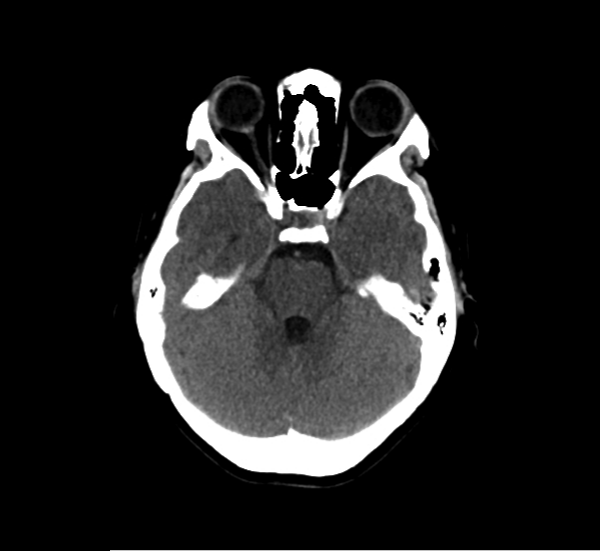

CT Brain Anatomy